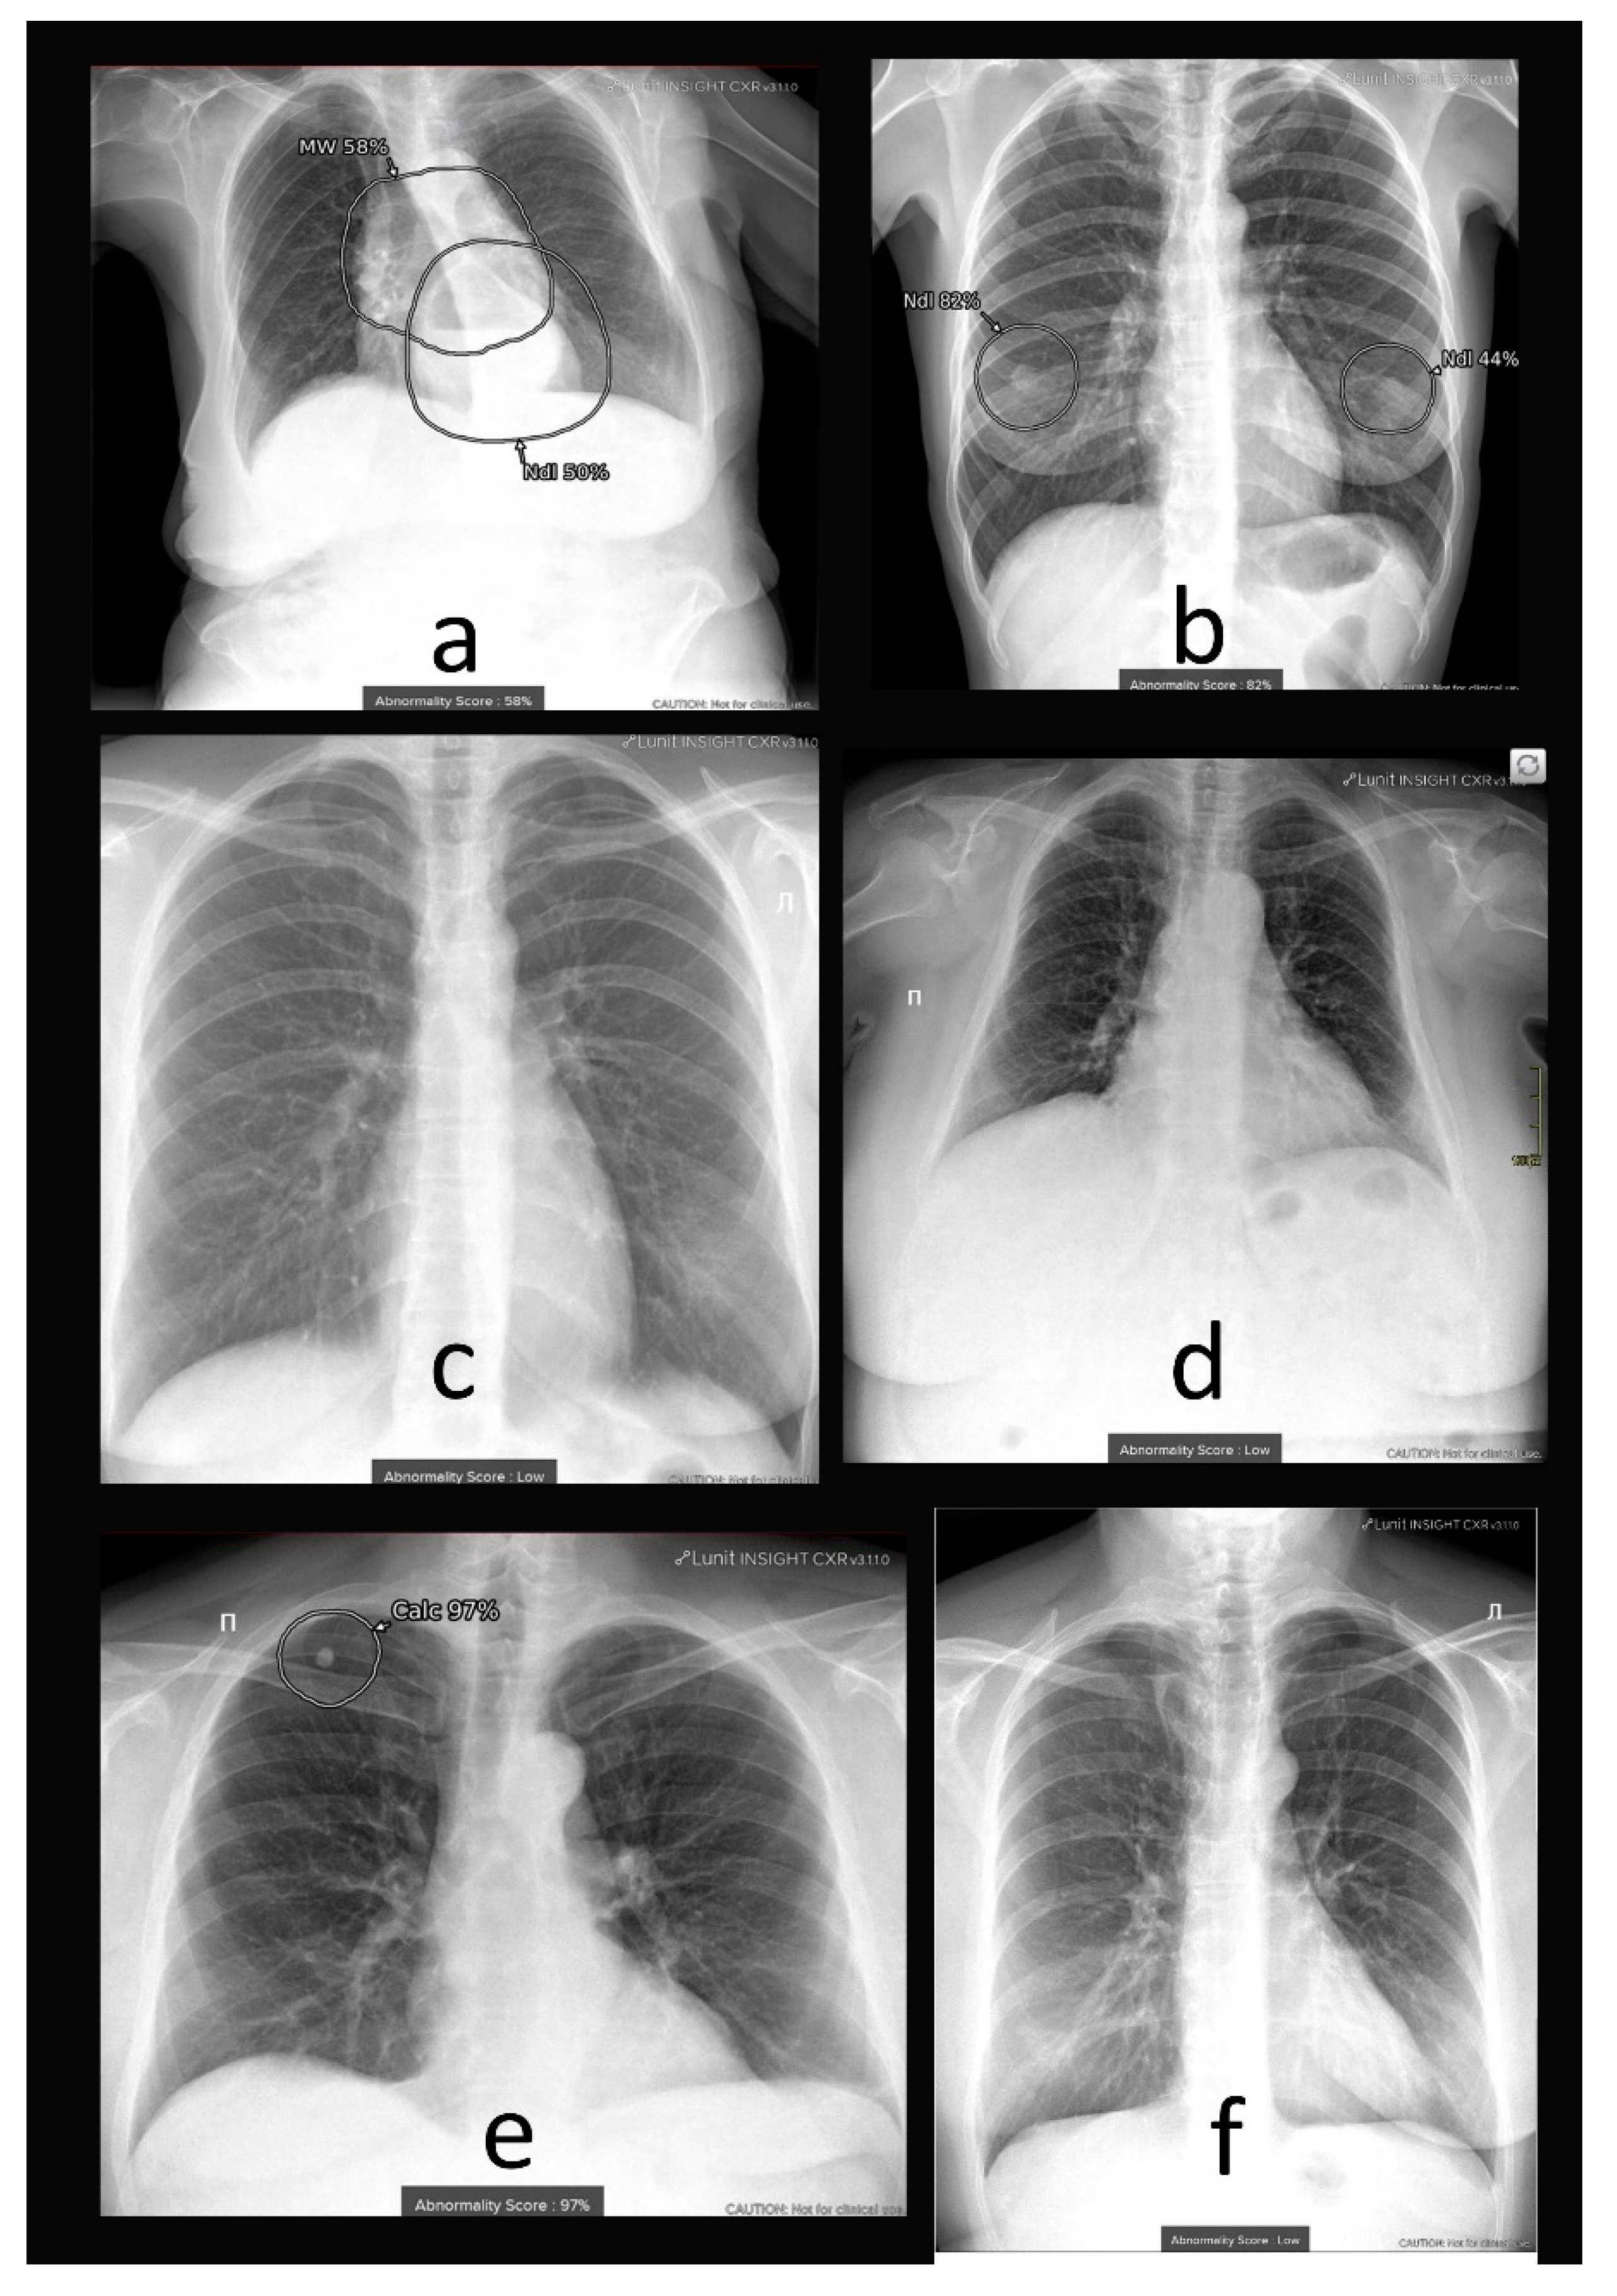

4.1. Additional Data and Technical Assessment of the Quality of Input CXR

4.2. Comprehensive Assessment of Identified Radiographic Features